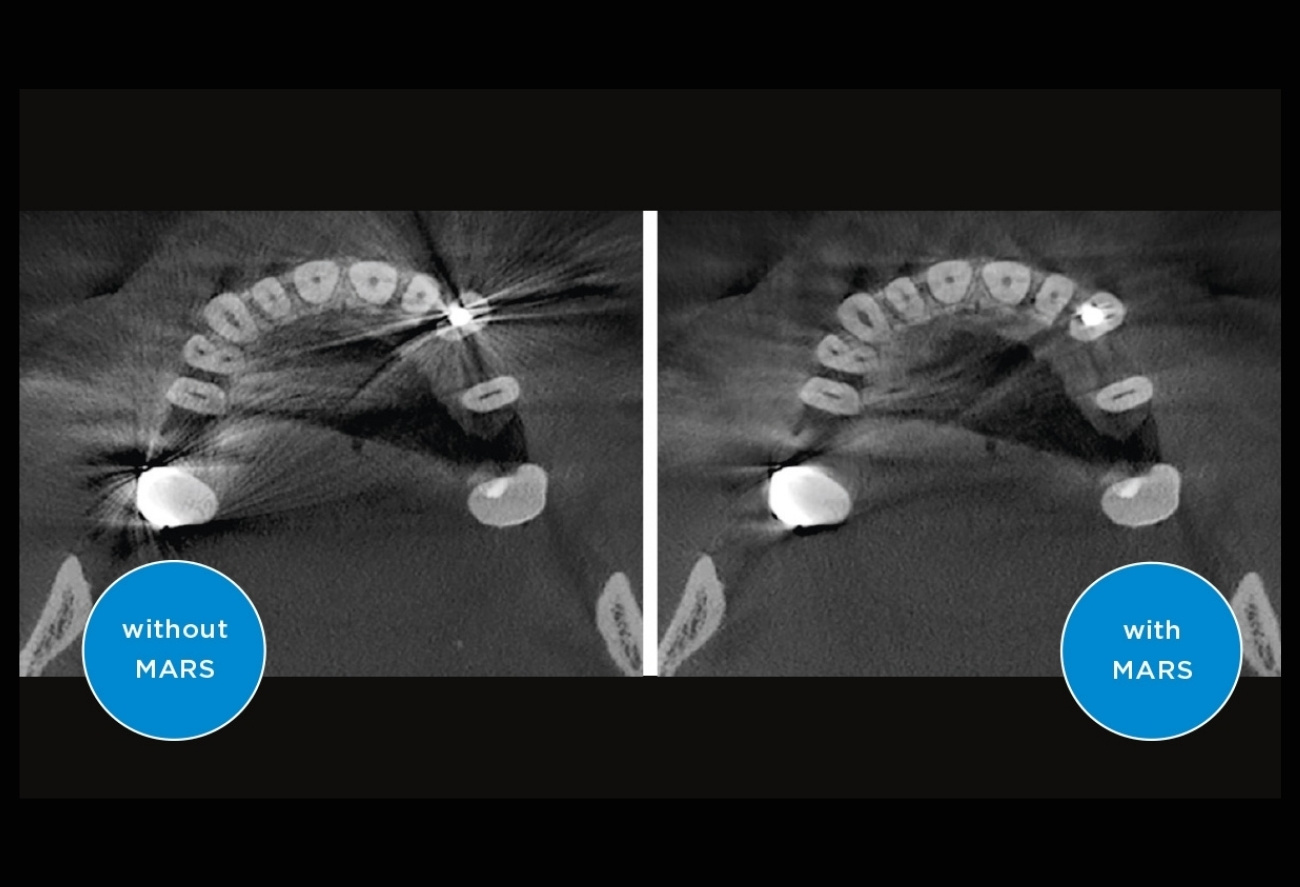

Приклади 3D-зображень: